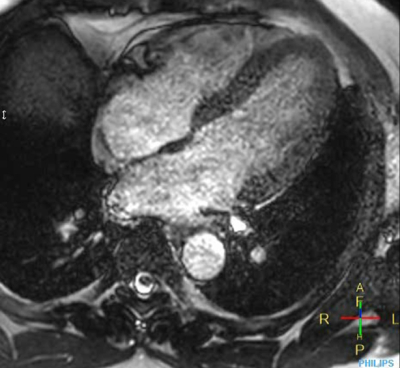

Cine 2D BFFE (4 CAV)

Elition X 3.0T